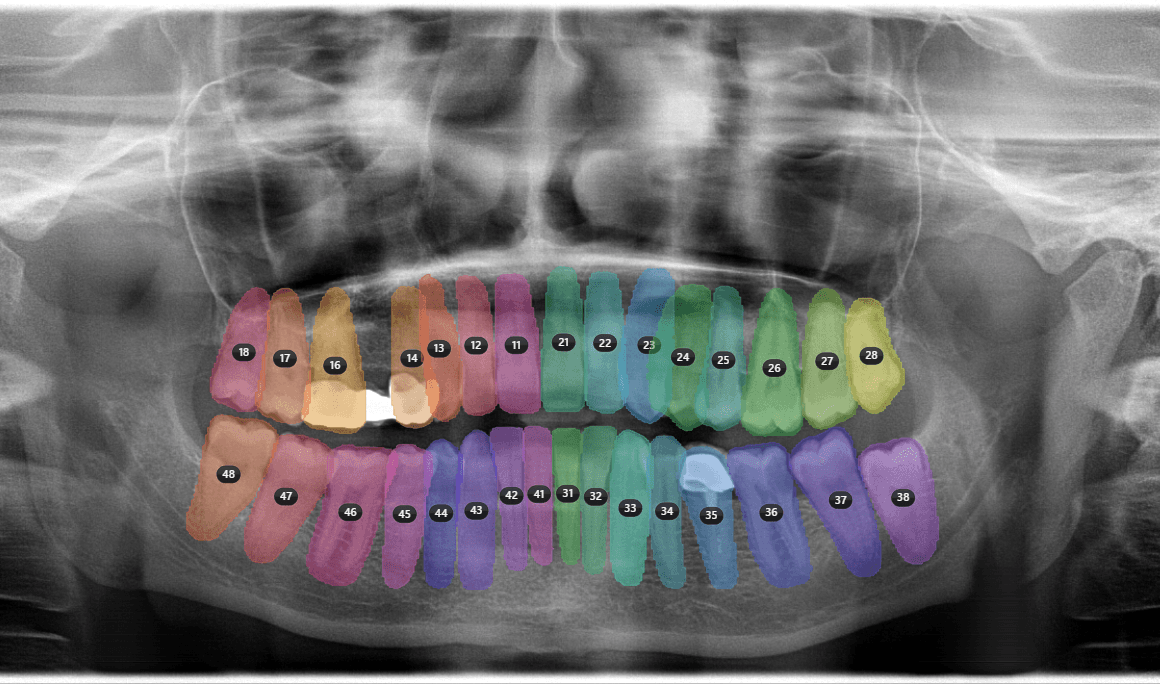

04Teeth Detection & FDIMay number visible teeth using FDI notation (11-48) and associate candidate observations with positions

FDI Map

Candidate observationTooth 36

AI 2DClinician review85%

Accept

Reject

Edit